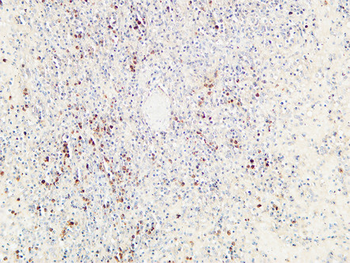

IHC staining of FFPE human lymph node with CD72 antibody (clone BU40). HIER: boil tissue sections in pH9 10mM Tris with 1mM EDTA for 20 min and allow to cool before testing.

IHC staining of FFPE human lymph node with CD72 antibody (clone BU40). HIER: boil tissue sections in pH9 10mM Tris with 1mM EDTA for 20 min and allow to cool before testing.